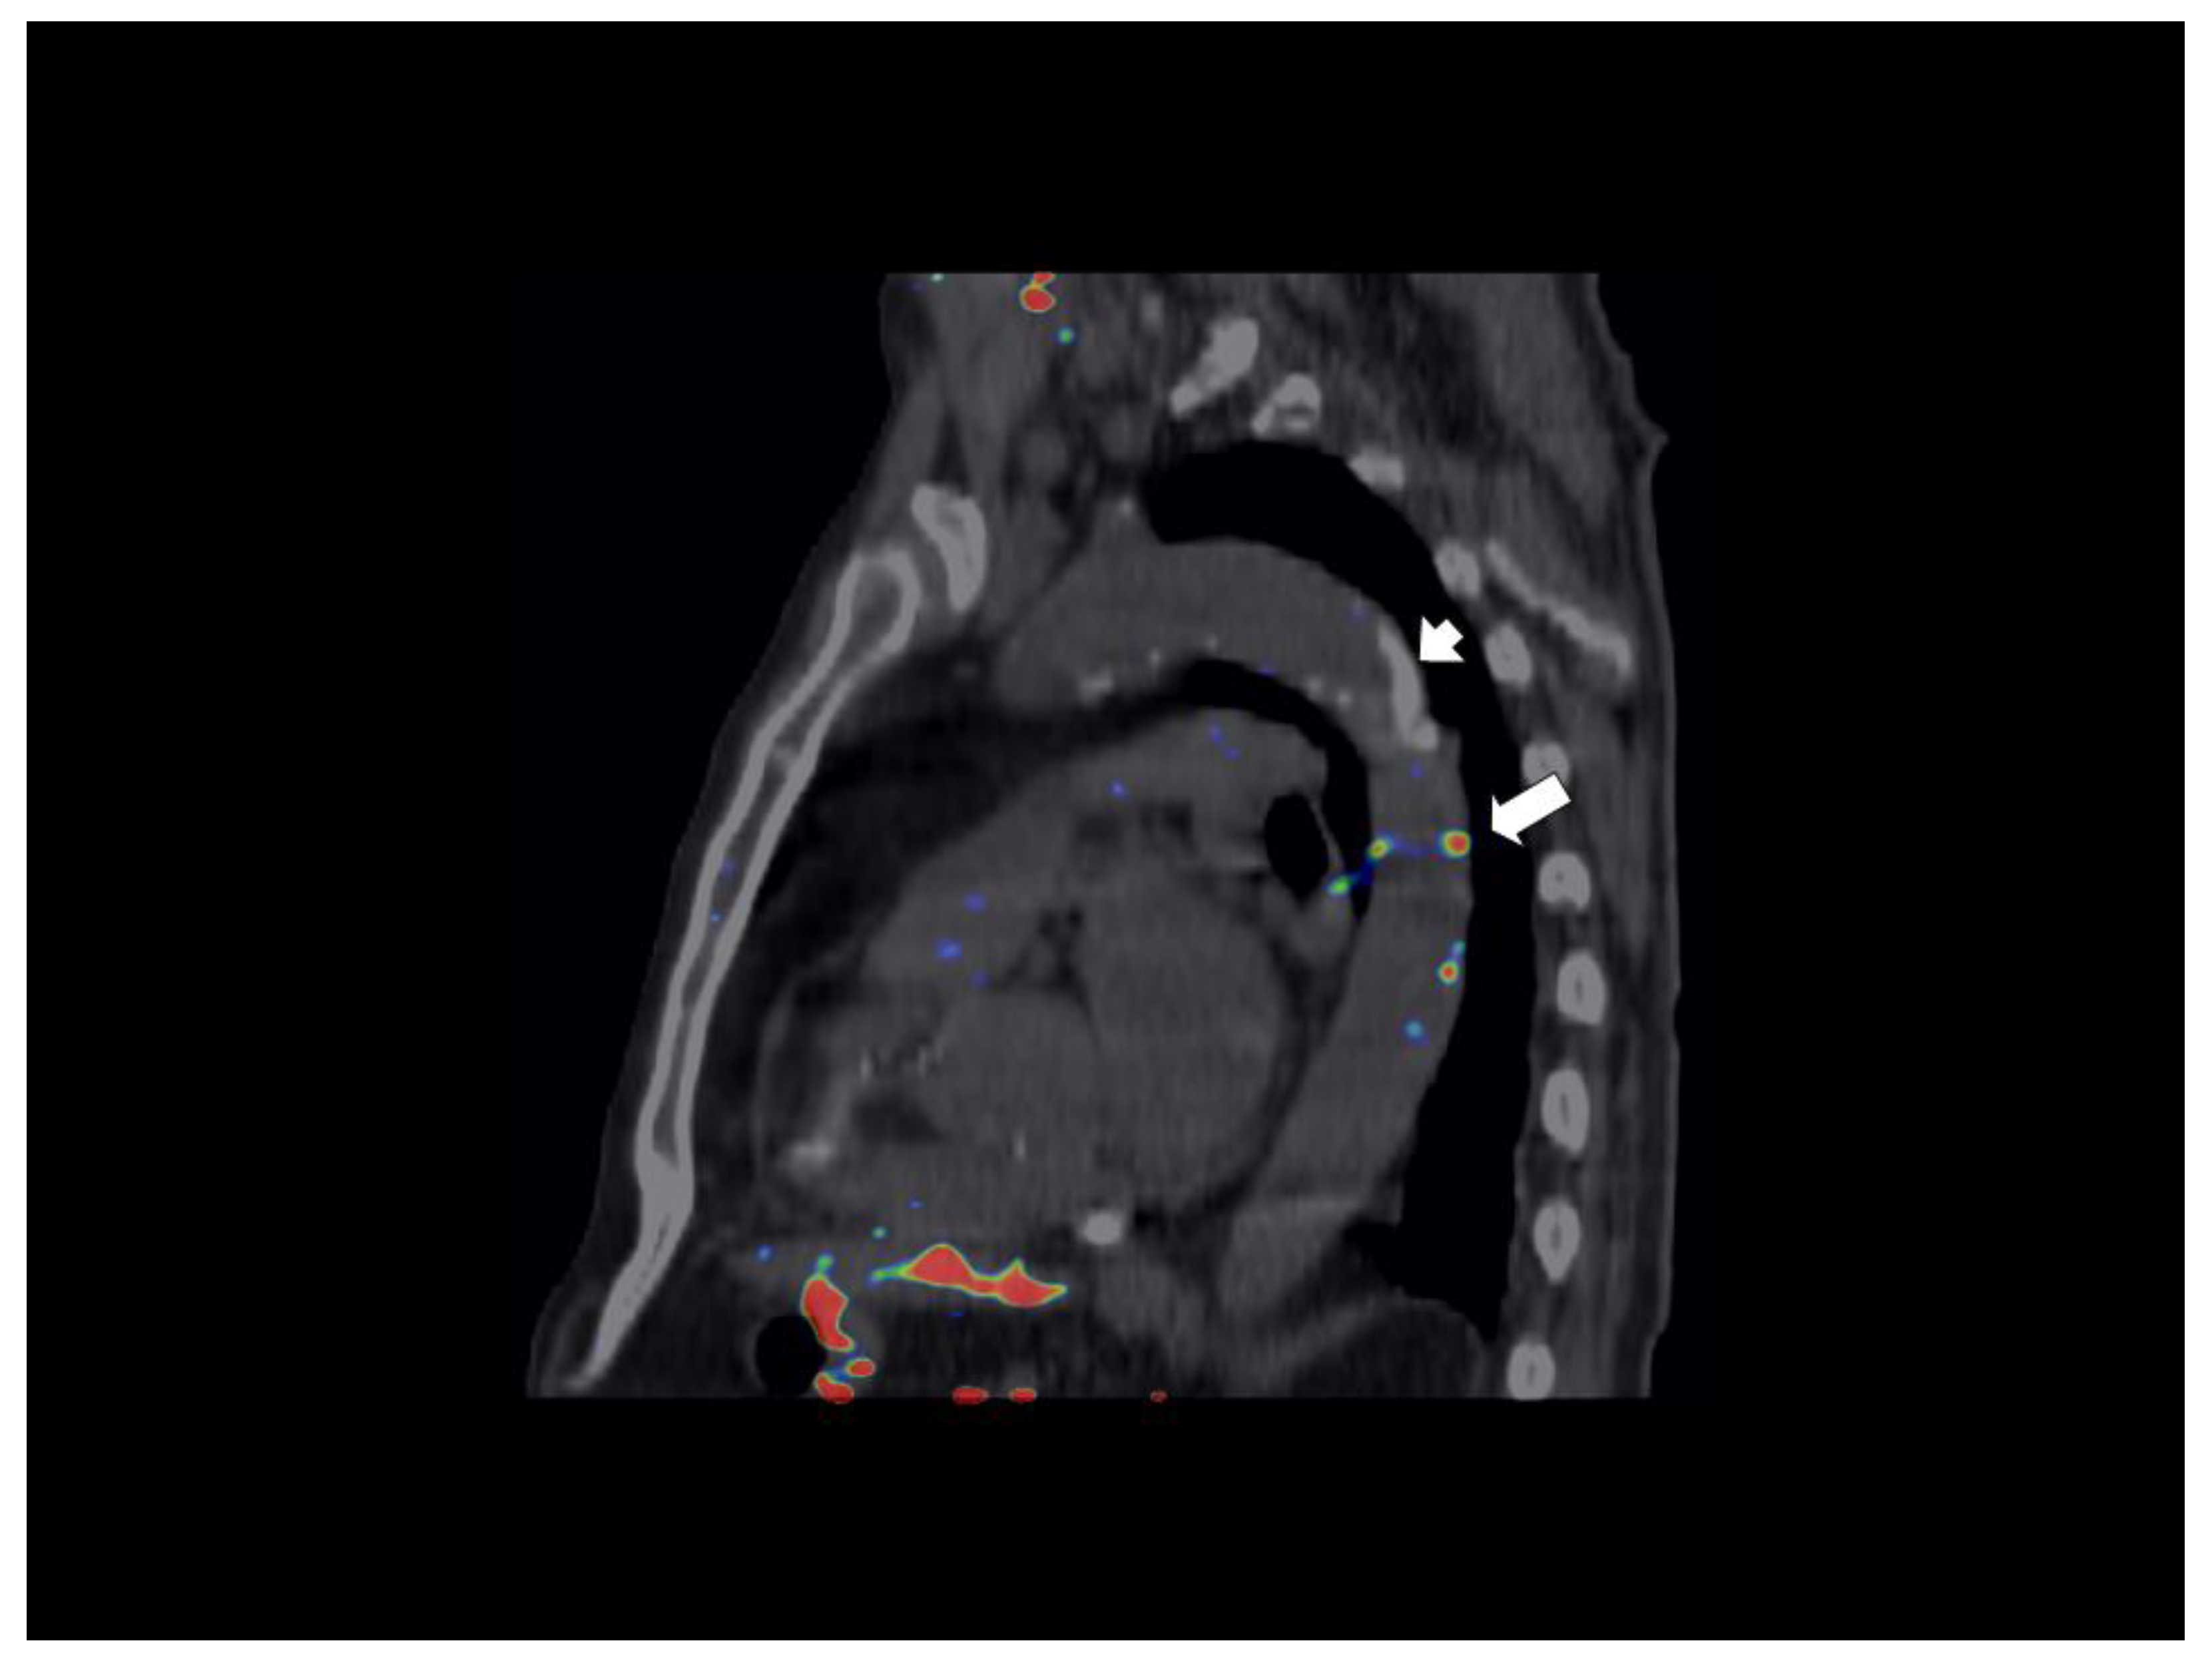

Table 2 shows that there were no differences in terms of OCT-assessed features of coronary plaque vulnerability between the two study groups. Overall, patients with low levels of cystatin C were more likely to have a higher FDG uptake in the aortic wall and CAC score. When modelled as continuous variable, cystatin C levels showed a strong trend towards an inverse relationship with the number of active slices in DA (rho = −0.35, p = 0.06). Yet, after multivariable analysis, levels of cystatin C were independently associated with FGD uptake in DA as measured by either averaged max TBR or number of active slices (Table 3). Figure 2A depicts a 18F-FDG-PET/CT scan from a patient in the high cystatin group showing no significant FDG uptake in the DA (max TBR = 1.3), whilst a further 18F-FDG-PET/CT scan from a patient in the low cystatin C group shows an active (max TBR = 2.0) focus of FDG uptake in the DA wall (Figure 2B). There were no active slices in the AA, in both cases. Finally, no trend was found for the association of cystatin C and CAC score. Figure 3 shows that areas of FDG uptake in the aortic wall are not related to the presence of calcification.

Figure 2.

Representative 18F-FDG-PET/CT image of thoracic aorta. (A) 18F-FDG-PET/CT image from a patient in the high cystatin C group (cystatin C = 1.38 mg/mL) showing a non-significant focus (arrow) of 18F-FDG uptake in the descending aortic wall with a TBRmax of 1.3 (18F-FDG-PET slices are defined as active if TBRmax is ≥1.6) (B) 18F-FDG-PET/CT image from a patient in the low cystatin C group (cystatin C = 0.84 mg/mL) showing an active focus of 18F-FDG uptake in the descending aorta with a TBRmax of 2.0 (arrow) and a non-active focal 18F-FDG uptake (arrowhead; TBRmax = 1.5) in the ascending aorta. Abbreviations: 18F-FDG-PET/CT = 18F-fluorodeoxyglucose-positron emission tomography/computed tomography; LV = left ventricle; TBR = target to background ratio.